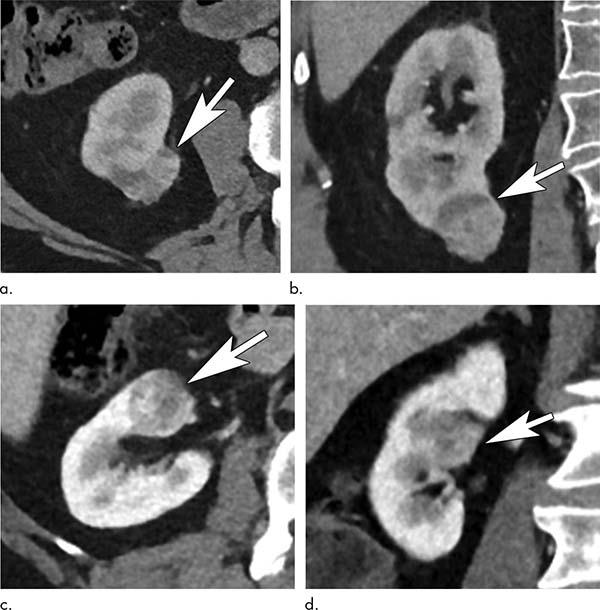

Figure 4

Figure 4: Renal tumors show low and high anatomic complexity. Contrast-enhanced (a) axial and (b) coronal abdominal CT images in a 70-year-old man diagnosed with a right renal tumor (arrows) Nephrometry score of 4 indicated noncomplex tumor anatomy. In the setting of mild (stage 2) chronic kidney disease, the Renal Anatomy and Function for Indeterminate Renal Mass model results would favor partial nephrectomy. Axial (c) and coronal (d) CT images in a 70-year-old man diagnosed with a centrally located renal neoplasm (arrows). The nephrometry score of 10 indicated high anatomic complexity because of interpolar location and contact with the collecting system and renal hilar vessels.